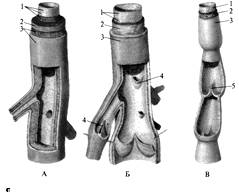

Строение стенок артерий. Особенности

эластических, мышечных и смешанных артерий

Кровеносные сосуды, идущие от сердца к органам и

несущие к ним кровь, называются артериями. Стенка артерий (рис. А) состоит из

3-х оболочек: 1 – tunica intima – внутренняя оболочка образована эндотелием, 2

– tunica media – представлена гладкой мышечной тканью и эластическими

волокнами, 3 – tunica externa – содержит соеденительнотканные волокна.

Особенности строения вен

Стенки вен (рис. Б) устроены как артерии (рис.

А), но в них меньше эластической и мышечной ткани, поэтому пустые вены